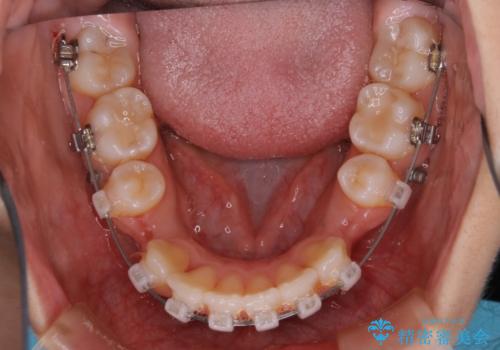

- 矯正装置

- ワイヤー(クリア装置)

ガタつきの度合いは軽度でしたが歯列の幅が狭く、その分前歯が上下とも前方に出てしまっていました。

しっかりと口元・顔貌まで変化を起こせるように上下左右の第一小臼歯を抜歯し、ワイヤー装置にて矯正を開始することとなりました。